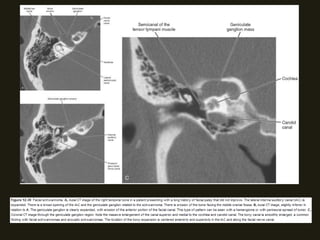

SCHANOMAS DOS NERVOS FACIAIS

• Mais comuns no gânglio geniculado, labirinto e segmentos timpânicos;

• Sintomas – diminuição da acuidade auditiva, paralisia facial...

• RM – lesão isointensa T1 e iso/hiperintensa em T2;

• TC – erosões ósseas da porção antero-superior do CAI e do gânglio

geniculado são sugestivas;

• Pode disseminação extracanicular – massa tumoral localizada além do

canal do nervo facial, na área supralabiríntica, orelha média, mastóide,

parótida;